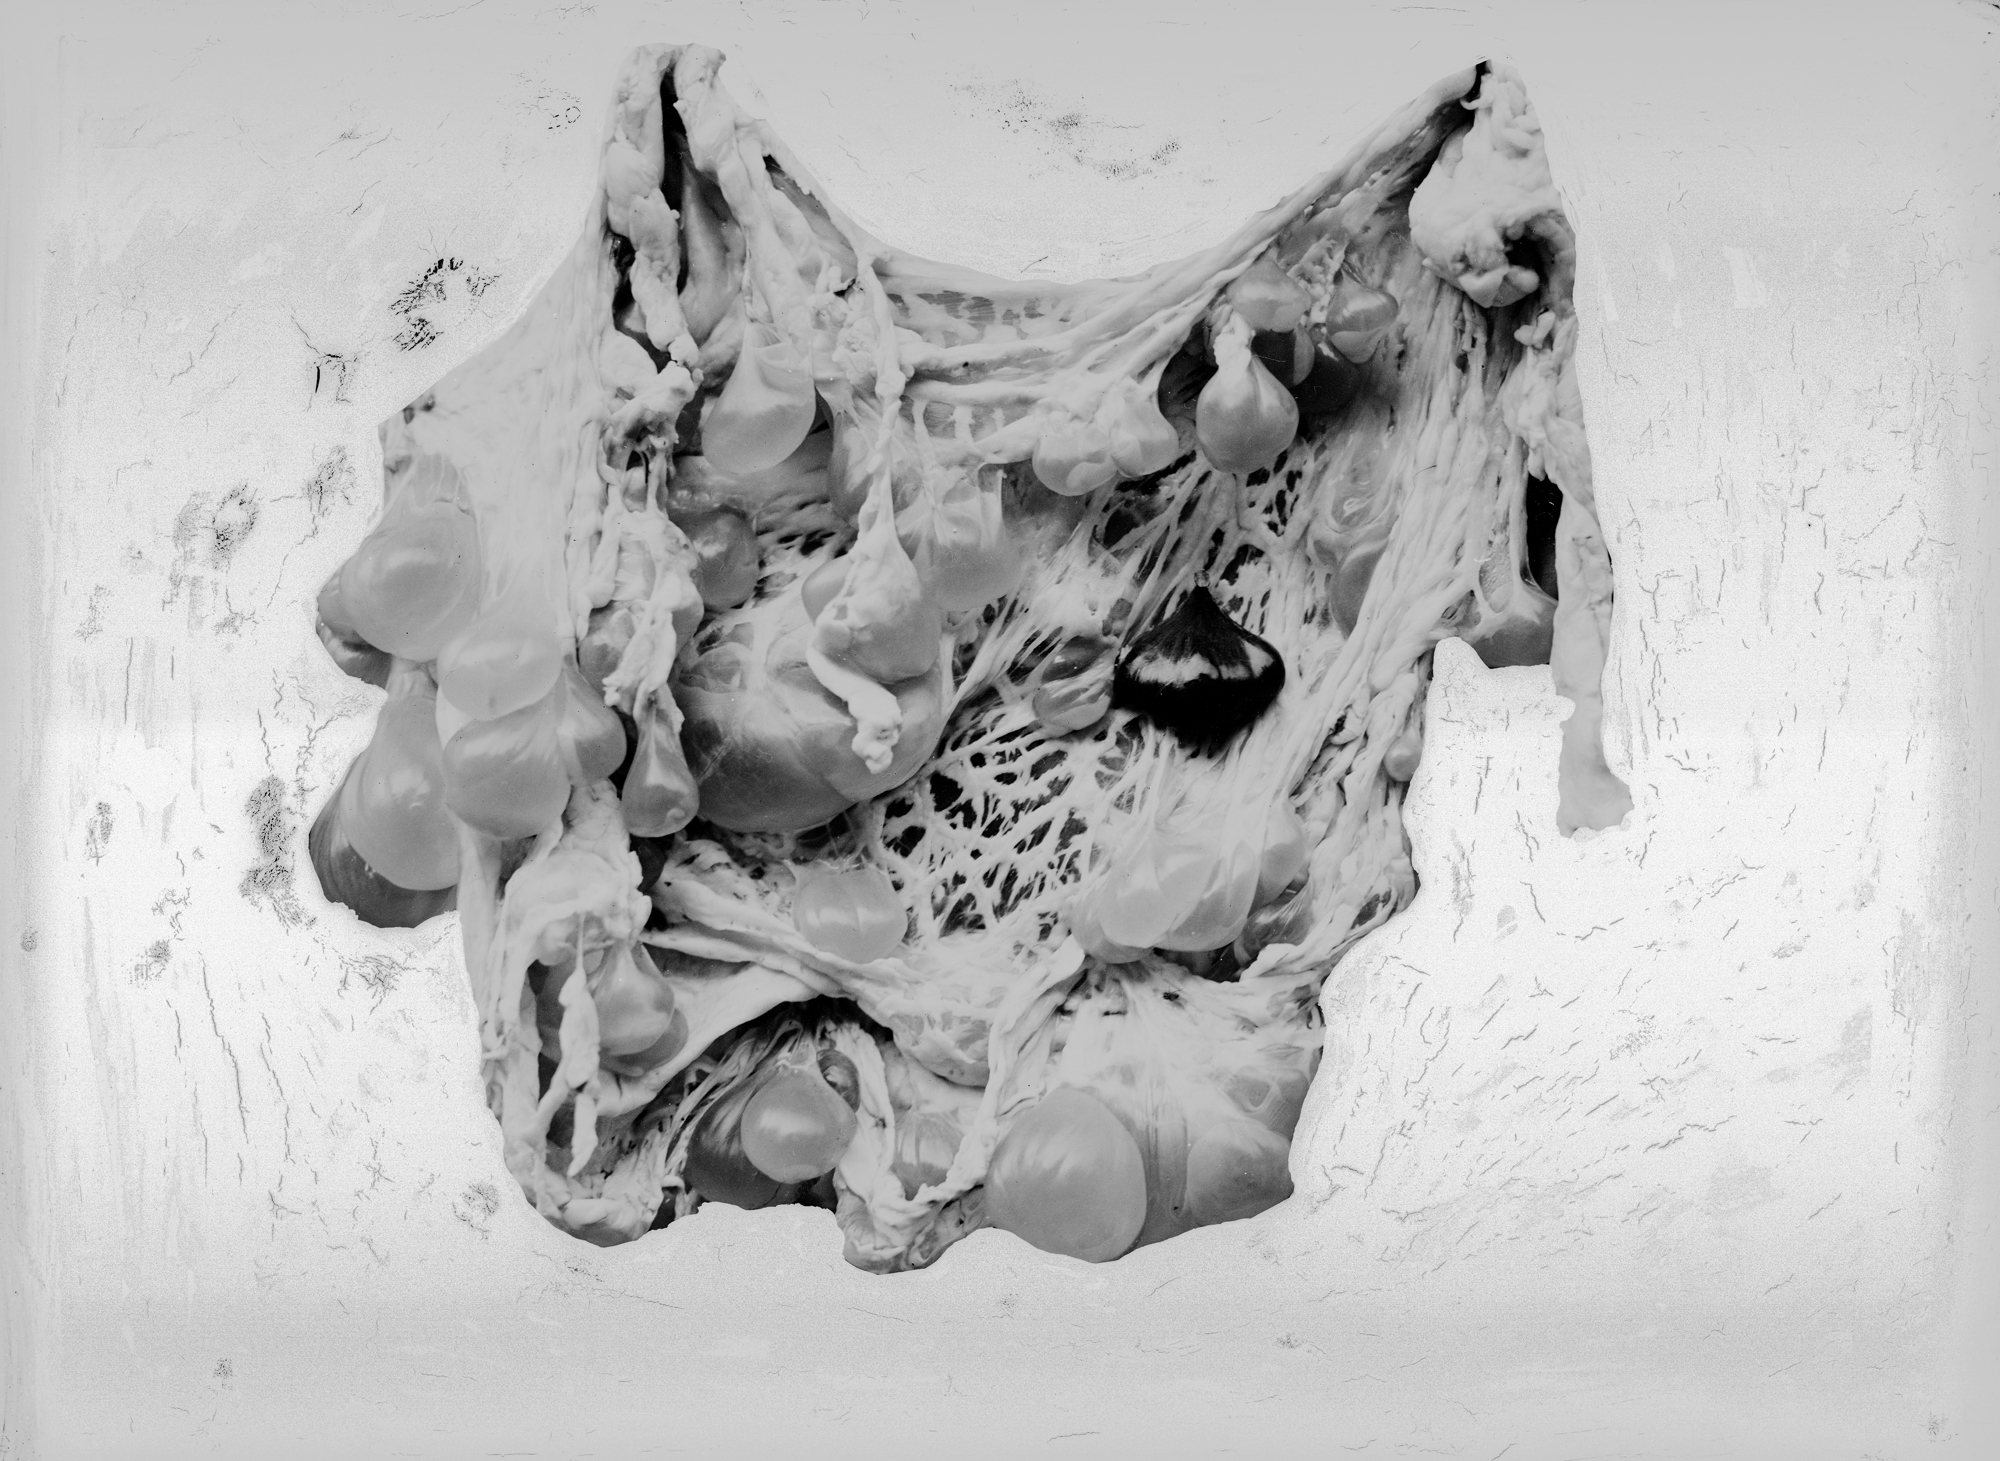

Pathological specimens of Hydatid cysts

January 1921–December 1935